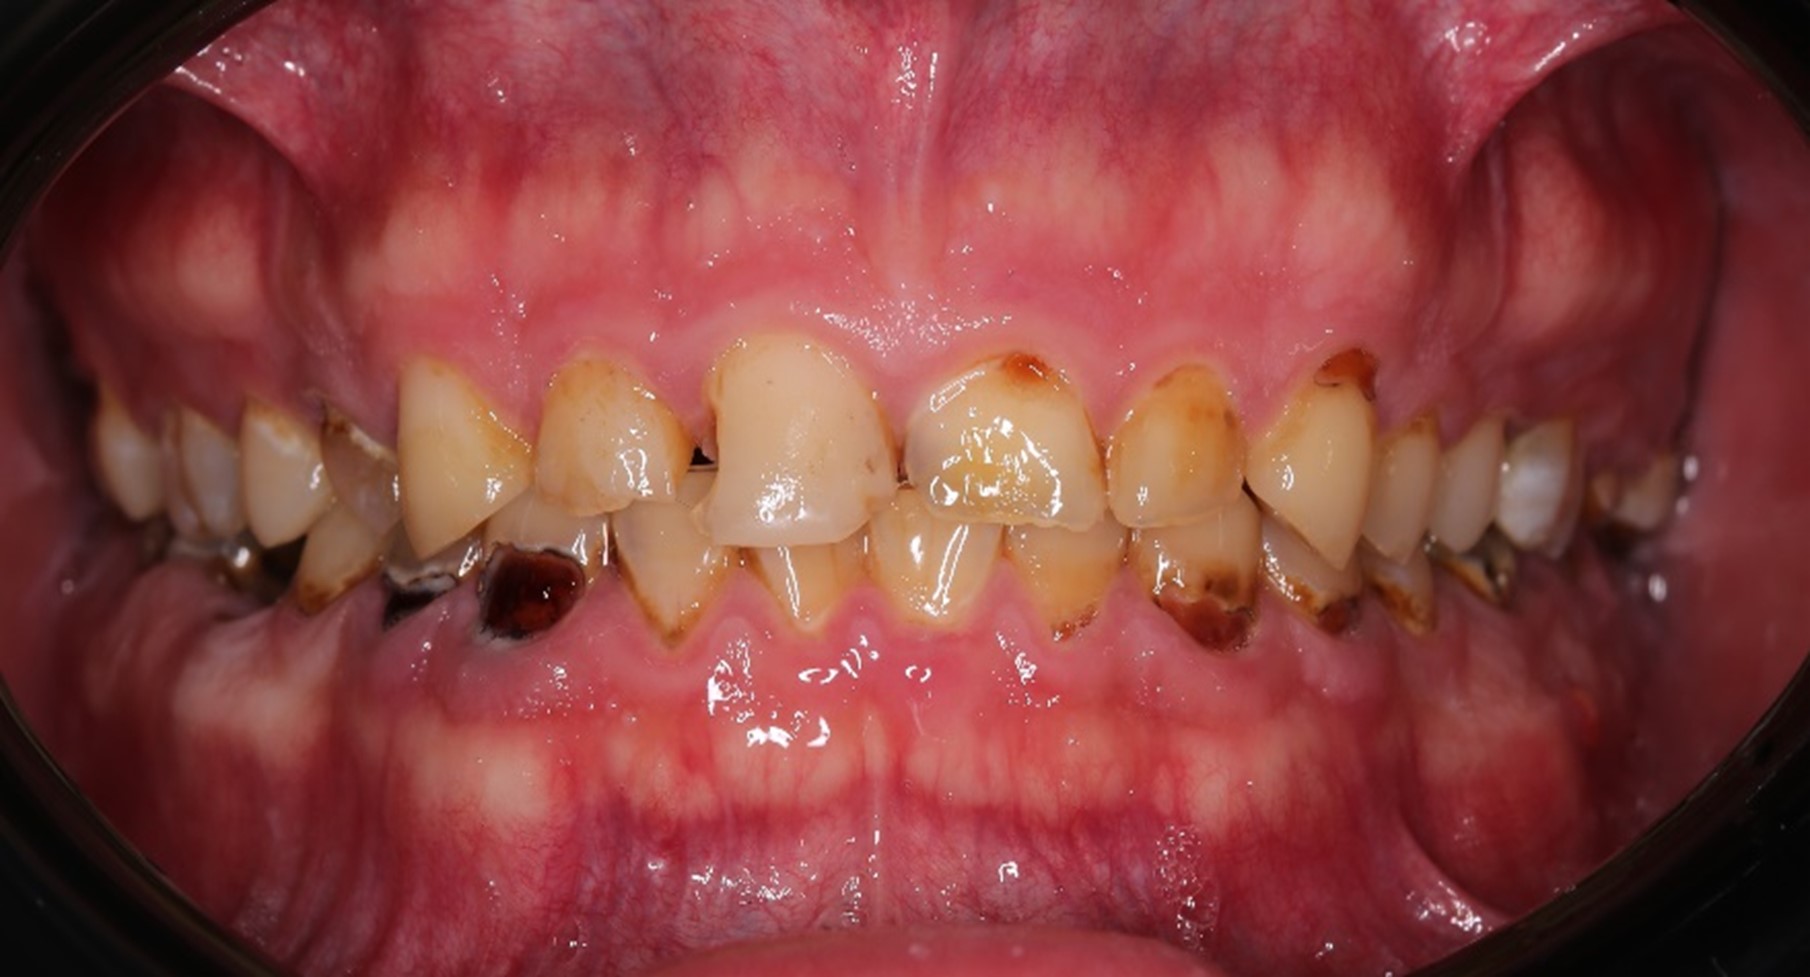

Напоминаю: он пришёл к нам вот в таком состоянии:

Жалобы были не только на внешний вид зубов, но ещё и на проблемы с дыханием и приёмом пищи. Общаться с людьми было тоже некомфортно.

Во-первых, нам нужно было сохранить как можно больше живых зубов при условии, что ни одного целого не было: везде либо вторичный кариес под пломбами, либо сколы, либо стёртые зубы, либо сильно разрушенные. А на фронтальной группе — всё это сразу.

В жевательном отделе зубов практически нет. На зубах с первого по пятый появились небольшие фасетки стираний, которые означают, что прикус зафиксирован именно на них. Если они настолько отчётливые, как у Ивана, это значит, что зубы начинают стираться, и высота нижнего отдела лица уменьшается. Значит, придётся повышать прикус, чтобы вернуть височно-нижнечелюстной сустав и зубы в первоначальную здоровую позицию. Это будет моей задачей.